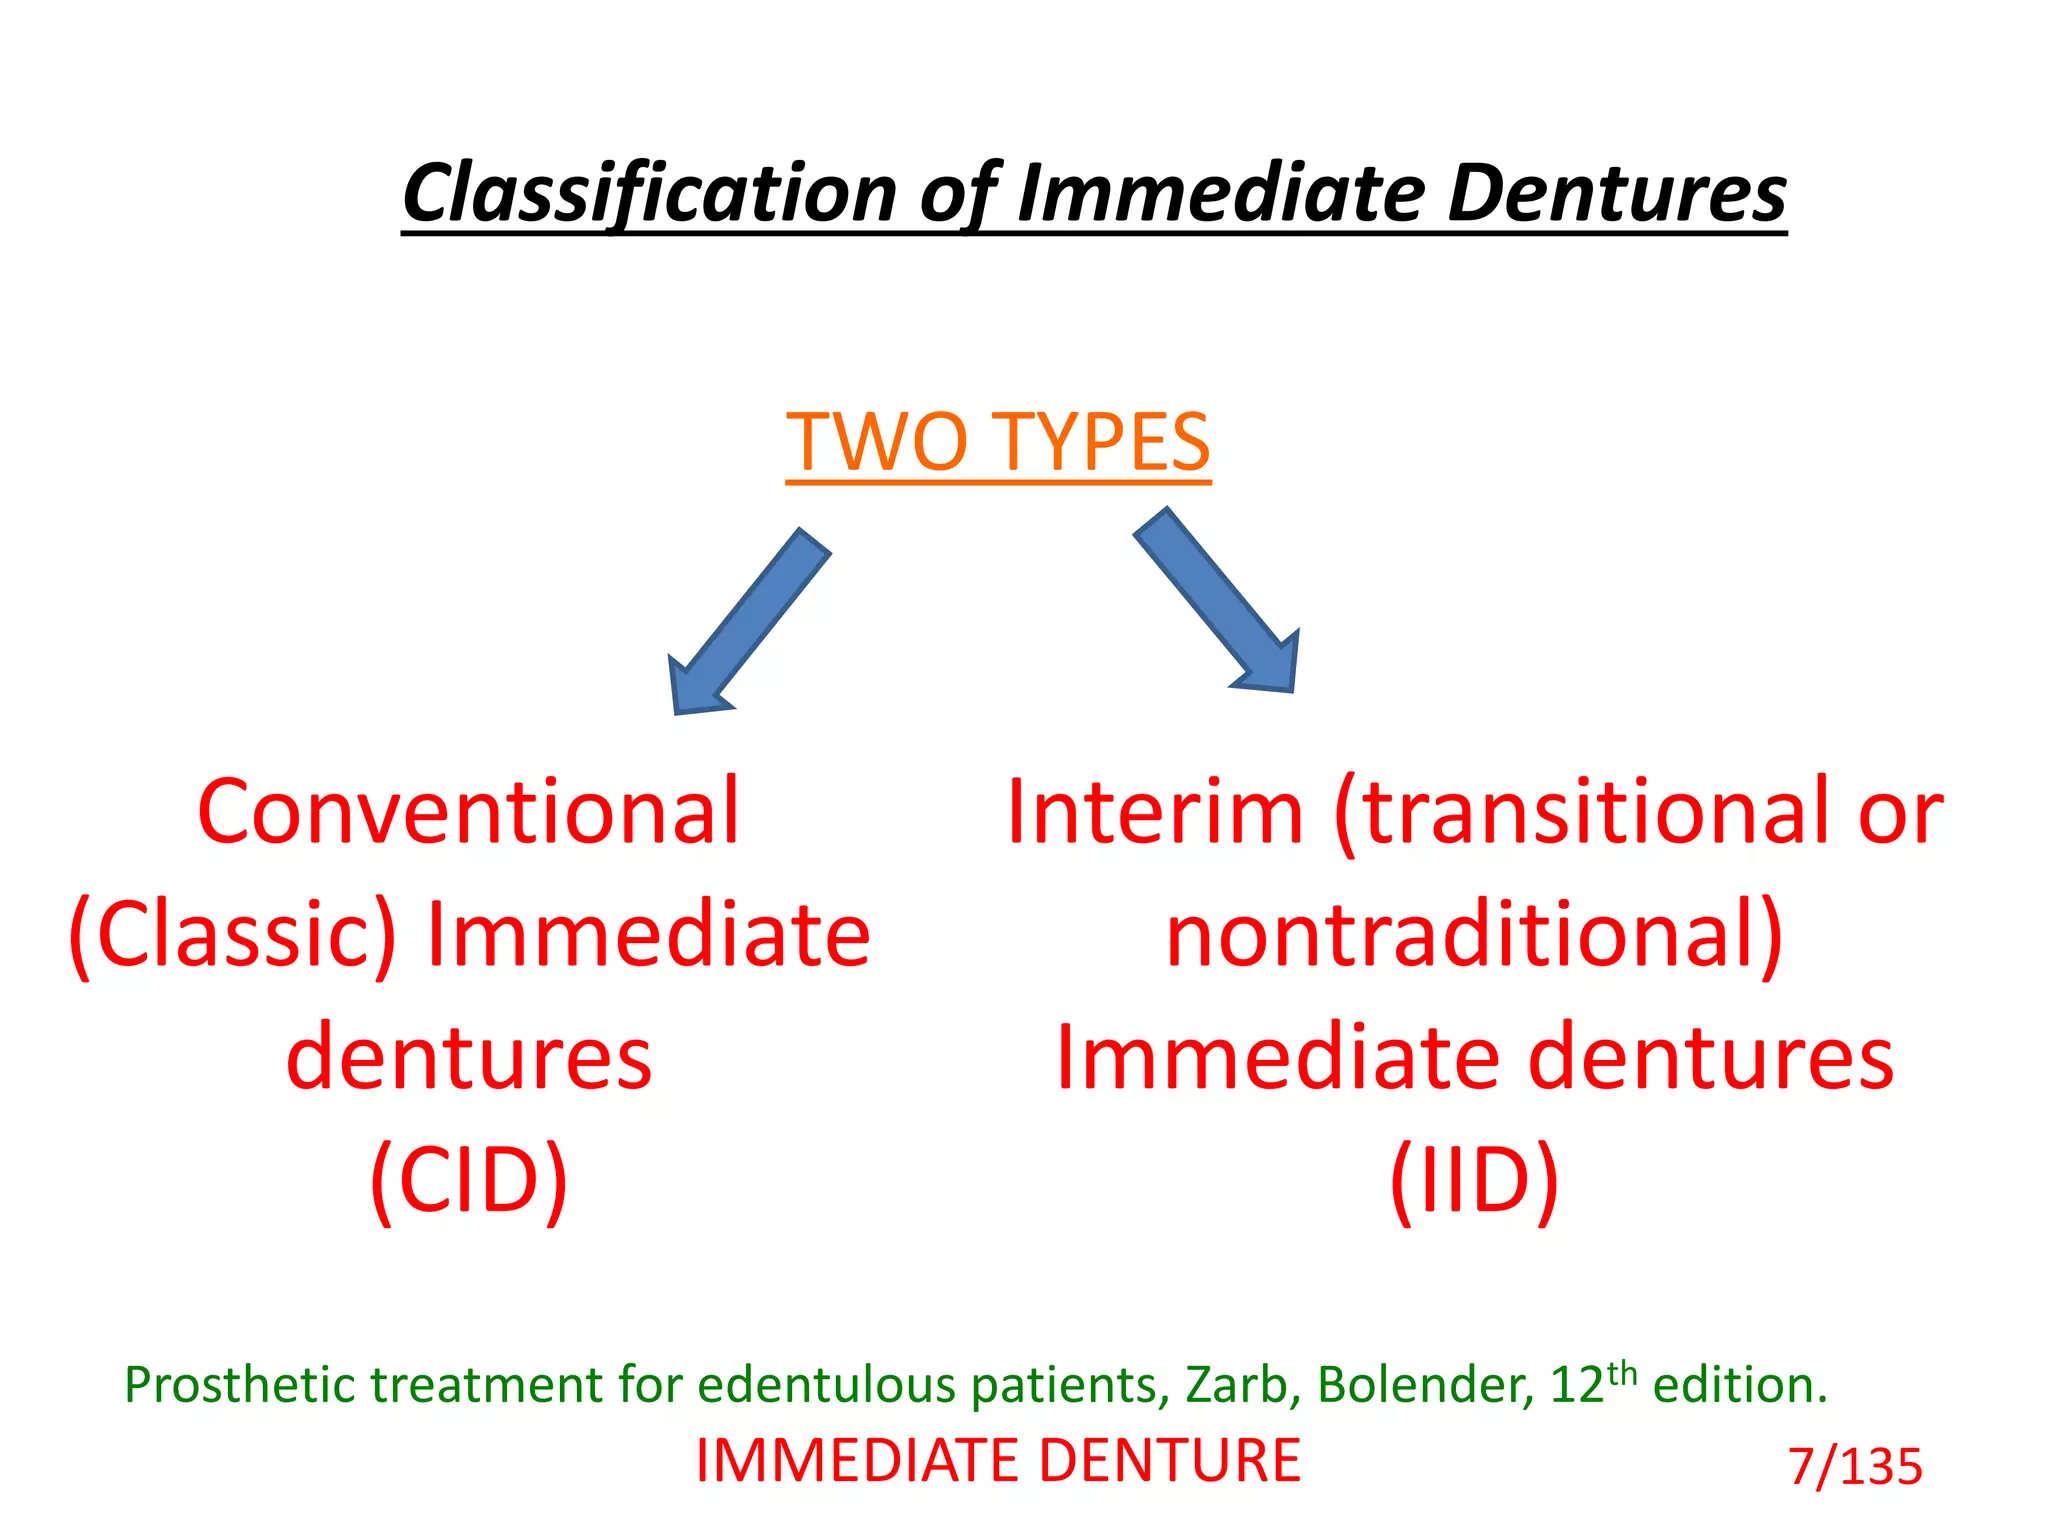

The document discusses immediate dentures, which are dentures fabricated and inserted immediately following tooth extraction. It describes the different types of immediate dentures, including conventional/classic immediate dentures, interim immediate dentures, labial flange dentures, partial flange dentures, and flangeless/socketed dentures. The advantages of immediate dentures include maintaining a patient's appearance without teeth, providing a bandage effect to extraction sites, and allowing easier adaptation to dentures during healing. However, immediate dentures also present challenges like reduced retention from undercuts caused by remaining posterior teeth.